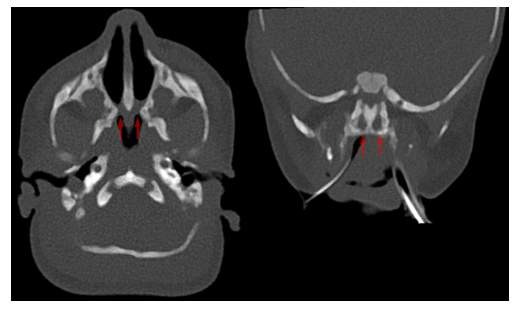

Choanal atresia

Choanal atresia is a congenital disorder where the back of the nasal passage (choana) is blocked

– It is due to problems in the bony and soft tissue leads to obstruction of the nasal passage

– It usually presents at birth and is associated with having other defects like learning disabilities and colobomas

Diagnosis:

– Clinical Examination

– CT scan is used to provide definitive diagnosis

Management:

– Surgery (fenestration procedures) to open the airway and keep it patent

Image 1: Hellerhoff, CC BY-SA 3.0 , via Wikimedia Commons